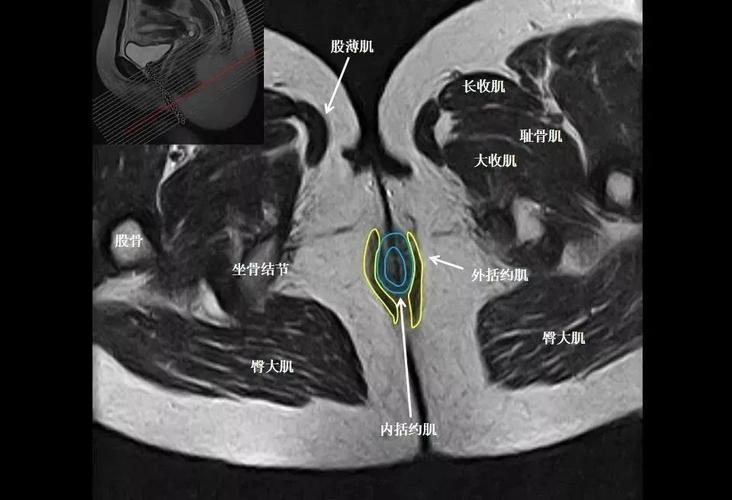

盆腔MRI解剖图

盆腔MRI解剖图,子宫mri正常解剖图谱

骨盆肌肉mri断层解剖

张8图带你熟悉盆底mri解剖

【ppt】骨盆肌肉解剖mri标识